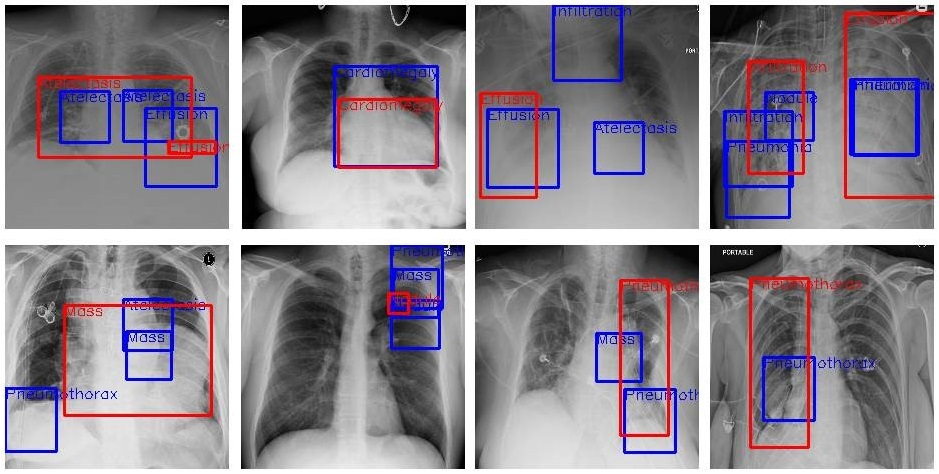

Unleashing the Power of Generative AI in Medical Imaging

Medical imaging is an indispensable tool in modern healthcare, aiding in the diagnosis, treatment planning, and monitoring of various medical